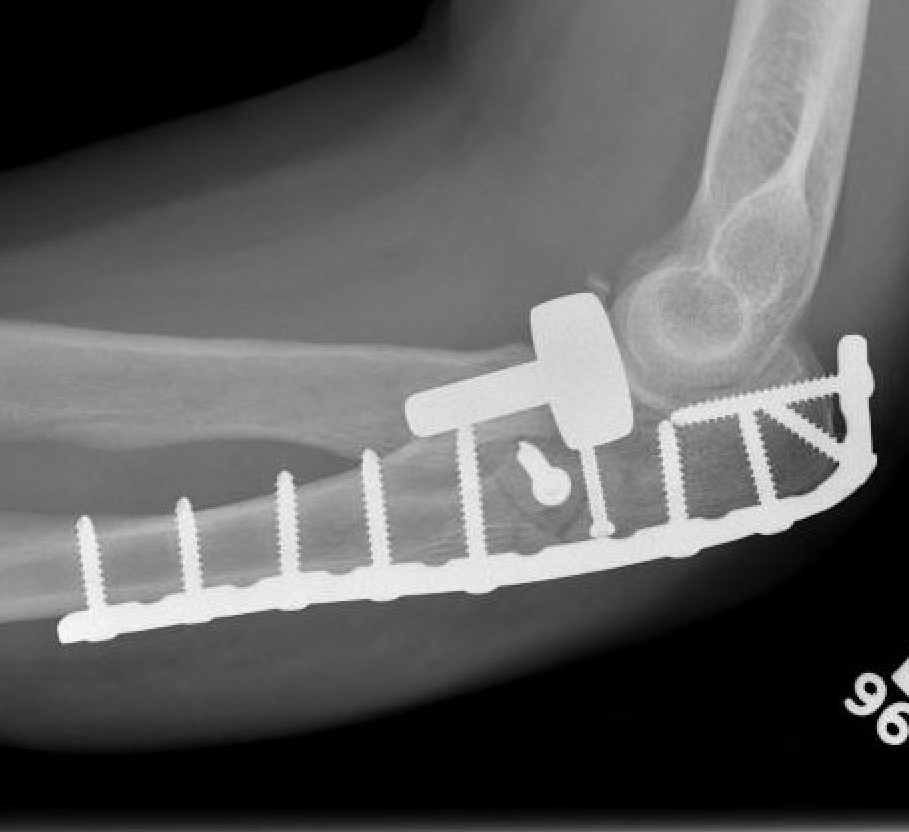

Olecranon plate + ORIF Type II coronoid process + radial head replacement

Olecranon plate with radial head replacement

Olecranon plate with radial head replacement + LCL repair

Olecranon plate + medial coronoid buttress plate + radial head replacement